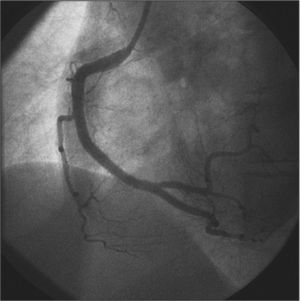

CASE REPORTThe case of a 38-year-old female patient with myocardial infarction with non-ST-segment elevation (NSTEMI) and without the classic risk factors for coronary artery disease is reported. She had a family history of one sister who died at 35 years of age from myocardial infarction associated with spontaneous dissection of the left coronary artery. In the week prior to admission, she had observed the onset of progressive chest pain in distress, at vigorous/moderate exertion, with relief at rest. On the day of the admission, she had an episode of angina of greater intensity and no improvement at rest, at the end of an exercise class, when she sought the emergency room of this hospital, and was attended to with pain initiated for at least 20 minutes. The electrocardiogram (ECG) showed no ST-T changes, and troponin I was elevated (1.03ng/mL, reference value<0.034ng/mL). The patient received treatment for non-ST segment elevation myocardial infarction (NSTEMI), with acetylsalicylic acid 300mg, clopidogrel 300mg, and subcutaneous enoxaparin; early invasive stratification was indicated. A coronary angiography was performed by right radial access (6F) within the first six hours of evolution, which showed preserved left ventricular function and end-diastolic volume, left coronary artery free of obstructive lesions, and right coronary artery with luminal narrowing from the middle third of the vessel, extending to the posterior ventricular and posterior descending branches, compromising up to 80% of the reference vessel diameter at the point of greatest narrowing (Figure 1).

– In A, right coronary artery in left anterior oblique view with significant luminal narrowing from the middle third of the vessel. In B, the right coronary artery in anteroposterior cranial view with severe narrowing involving the middle and distal thirds, as well as the proximal segments of posterior ventricular and posterior descending branches.